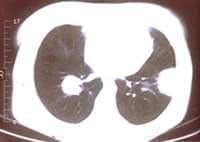

Bajo el diagnóstico clínico de Neumonía Adquirida en la Comunidad multilobar en paciente inmuno-comprometida se inició tratamiento intrahospitalario con Clindamicina, Ciprofloxacina, obteniéndose una respuesta clínica favorable por lo que se dio de alta a los ocho días de tratamiento. Debido a la persistencia de la imagen radiológica (Figura 3) aún finalizado el tratamiento, se tomó TAC de tórax (Figuras 4A y B).

Figuras 4A y B: TAC tórax: a nivel del segmento lateral basal del LII una opacidad redondeada de 4mm de diámetro mayor, de base pleural, con broncograma aéreo y cuatro imágenes nodulares en LID no calcificadas, sin broncograma aéreo.